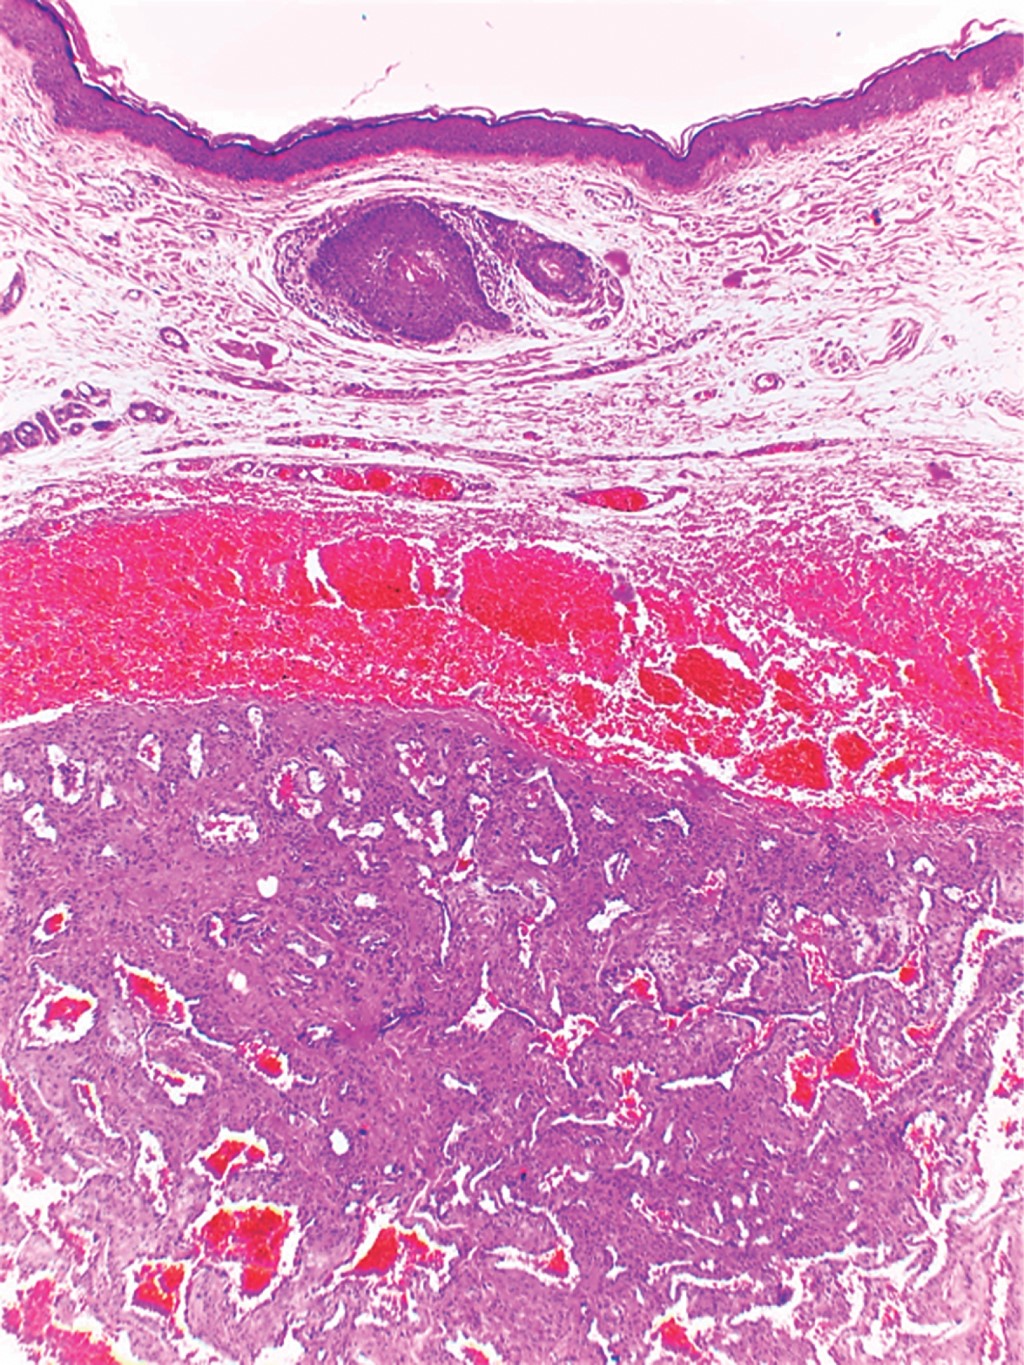

Se trata de un hombre de 69 años de edad, sin antecedentes de relevancia para el motivo de consulta, quien acude por presentar dermatosis localizada en cabeza, de la que afectaba pabellón auricular izquierdo a nivel de cara posterior del hélix, constituida por neoformación de 0.7 × 0.7 cm, hemiesférica, color azul-grisáceo, de superficie lisa, consistencia firme, bordes regulares, bien definidos; de dos años de evolución y sin síntomas asociados (Figura 1). A la dermatoscopía se observaron áreas azules sin estructura, con algunas zonas amarillentas y vasos lineales en la periferia (Figura 2). En el estudio histopatológico se observó epidermis con escasa capa córnea y tapones córneos. En la dermis superficial se observaron vasos dilatados rodeados por discretos infiltrados linfocitarios y zonas de edema entre las fibras de colágeno. En la dermis media y profunda se advierte la presencia de una neoformación circunscrita constituida por vasos dilatados y congestionados que se entremezclan con numerosas células fusiformes dispuestas en haces y que siguen diversos trayectos. La tinción tricrómica de Masson resultó positiva (Figuras 3, 4 y 5).

El abordaje diagnóstico puede incluir solicitar técnicas de imagen como el ultrasonido, que suele mostrar una masa ecogénica, homogénea, de bordes bien definidos y vascularizada.5,7 No obstante, estos hallazgos son inespecíficos y no permiten establecer el diagnóstico de forma certera, por lo que son necesarios la extirpación quirúrgica y el estudio histopatológico. Los hallazgos habituales con esta herramienta muestran una neoformación redonda, bien circunscrita, encapsulada, con haces de células musculares lisas entrelazadas y uniformes, distribuidas alrededor de vasos pequeños con paredes de calibre variable. Con frecuencia presentan degeneración mixoide, trombosis y calcificación distrófica.8 Con base en la morfología vascular, los angioleiomiomas pueden clasificarse en tres subtipos histopatológicos: sólido, venoso y cavernoso.9 En el venoso se observan vasos sanguíneos gruesos revestidos de músculo y haces de músculo liso intervascular.10 El sólido corresponde a 66% de los casos de angioleiomioma, seguido del venoso con 23% y el cavernoso con 11%.6

Figura 3